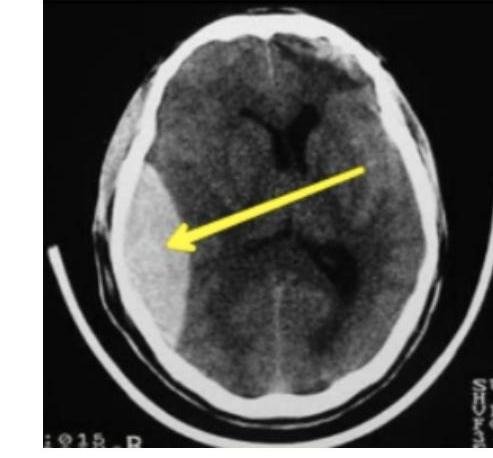

# TRAUMATISMO CRANEOENCEFÁLICO ## DEFINICIÓN Es una lesión directa en el cráneo, encéfalo o meninges por efecto mecánico provocado por un agente externo. Se clasifica en tres tipos: | TCE LEVE | Glasgow 14-15 | Cefalea leve, menos de 3 vómitos, sin pérdida de la conciencia | | :--------------: | :---------------------------------------------: | :----------------------------------------------------------------: | | TCE MODERADO | Glasgow 9-13 | Cefalea intensa, más de 3 vómitos, pérdida del estado de alerta, alteración de la conciencia, amnesia postraumática, convulsiones, sospecha de maltrato infantil, politraumatizado o trauma facial | | TCE GRAVE | Glasgow 8 o menor | Focalización, lesión penetrante del cráneo, fractura hundida o expuesta, disminución de Glasgow inicial, déficit neurológico de aparición posterior | **LESIÓN PRIMARIA**. Es el daño directo causado por el **impacto** del trauma o por los mecanismos de **aceleración-desaceleración**. Incluye **contusión cortical**, **laceración cerebral**, **fractura de cráneo**, **lesión axonal**, **contusión del tallo**, **desgarro dural o venoso**, etc. **LESIÓN SECUNDARIA**. Se desarrolla como consecuencia de la **injuria primaria**, desarrollando **sangrados**, **edemas**, **hiperemia**, **trombosis** y otros **procesos fisiopatológicos secundarios**. Incluye **hematoma intracraneano**, **epidural o subdural**, **edema cerebral**, **hipoxia y/o hipoperfusión cerebral**, elevación de **neurocitotoxinas** y **radicales libres**, **neuroinfección** y aumento de la **hipertensión endocraneana**. # EPIDEMIOLOGÍA - Es la causa más frecuente de coma (en ausencia de tumores o intoxicaciones). - Causa más frecuente de epilepsia en adolescentes y adultos jóvenes. ## FACTORES DE RIESGO - Causa y mecanismo de la lesión. - Tiempo transcurrido. - Estado mental subsecuente. - Presencia de crisis convulsivas postraumáticas. - Signos clínicos de fractura de cráneo. - Déficit neurológico específico. - Trastornos de la coagulación y uso de fármacos. - Sospecha de maltrato en menores de 18 años. ## ESCALA DE GLASGOW ADULTOS vs. NIÑOS | RESPUESTA OCULAR | | Puntos | | :---------------: | :--------------: | :------: | | **ADULTOS** | **LACTANTE** | | | Espontánea | Espontánea | 4 | | A estímulos verbales | A estímulos verbales | 3 | | Al dolor | Al dolor | 2 | | Ausencia de respuesta | Ausencia de respuesta | 1 | | RESPUESTA VERBAL | | | | **ADULTOS** | **LACTANTE** | | | Orientado | Sonríe, arrulla, gorgorea | 5 | | Desorientado / Confuso | Llora apropiadamente | 4 | | Palabras incoherentes | Grita, llanto inadecuado | 3 | | Sonidos incomprensibles | Quejido - gruñido | 2 | | Ausencia de respuesta | Sin respuesta | 1 | | RESPUESTA MOTORA | | | | **ADULTOS** | **LACTANTE** | | | Obedece órdenes | Adecuada al hablarle | 6 | | Localiza el dolor | Localiza el dolor | 5 | | Retira lo que le causa dolor | Retira lo que le causa dolor | 4 | | Flexión anormal | Flexión anormal | 3 | | Extensión anormal | Extensión anormal | 2 | | Ausencia de respuesta | Ausencia de respuesta | 1 | # MANEJO INICIAL DEL TCE ## TRAUMA LEVE (GLASGOW 14-15) Evaluación: Una vez documentado que se trata de un paciente con **TCE Leve**, se sabe que el riesgo de **complicaciones** es mínimo, por lo que el paciente no amerita **manejo intrahospitalario**. Monitorización: La **vigilancia** estará a cargo de los padres o **custodios** del menor en **DOMICILIO**. - La vigilancia de 6 horas en hospital es a criterio de decisión del médico. - No existe evidencia de que deba impedirse el **sueño** en las horas posteriores (incluso la falta de sueño puede modificar la conducta del paciente, dificultando la vigilancia de **datos de alarma**). - Se sugiere despertarlo cada 3 horas para evaluarlo. Indicaciones de una **NUEVA VALORACIÓN** (datos de alarma): - 3 o más vómitos en 24 horas. - Cefalea intensa. - Imposibilidad para establecer o mantener estado de despierto. - Crisis convulsivas. - Cambios en la conducta del menor. - Cualquier déficit neurológico (amaurosis, amnesia, paresia). - Presencia de hemorragia o salida de líquido por nariz u oído. - Marcha tambaleante o posturas anormales. TRAUMA MODERADO (GLASGOW 9-13) **VALORACIÓN E INVESTIGACIÓN EN URGENCIAS**: - **ABC**. - Deben ser valorados en un tiempo máximo de 15 minutos. - Si clínicamente se evidencia una lesión cerebral o de columna cervical, la valoración debe ser extensa. Criterios para realizar **RX**: - Menores de 1 año. - Sospecha de maltrato (complementar con huesos largos). - Pérdida de conciencia superior a cinco minutos (solo si no hay TAC). - Crepitaciones o hundimiento. - Trauma facial grave. - Rx Cervical indicada si hay politraumatismo, TCE Grave, dolor cervical (proyección antero-posterior). - No deben ser usadas como diagnóstico, solo de apoyo. # CRITERIOS PARA TAC INMEDIATA - Pérdida de conciencia de más de 5 minutos. - Amnesia anterógrada o retrógrada de más de 5 minutos. - Letargia. - 3 o más vómitos. - Convulsiones postraumáticas (sin antecedente de epilepsia). - Glasgow <15 en menores de 1 año y Glasgow <14 en el resto de pediátricos. - Sospecha de lesión abierta o deprimida (fontanela tensa). - Cualquier signo de fractura de base del cráneo. - Déficit neurológico focal. - Si es menor de un año: hematoma, edema, laceración de +5 cm en cabeza. - Mecanismo peligroso: accidente de alta velocidad, caída mayor a 3 metros, daño de alta velocidad con proyectil. - Coagulopatía (antecedente de sangrado o anticoagulantes). ## CRITERIOS PARA RMN: - No se indica como método primario de investigación para lesión cerebral secundaria a TCE. - Puede otorgar información adicional para el pronóstico (detecta lesiones pequeñas que no se ven en TAC). ## CRITERIOS PARA INTUBACIÓN EN TCE PEDIÁTRICO: - Escala de coma de Glasgow menor a 10 (adultos < 8). - Disminución de Glasgow de +3 puntos posterior a una calificación inicial. - Coma. - Anisocoria > 1 mm. - Lesión cervical espinal que comprometa ventilación. - Apnea. - Pérdida de reflejos de protección laríngea. - Hipercapnia (PaCO2 > 45 mmHg) o Hipoxemia (PaO2 < 60 mmHg). - Hiperventilación espontánea que ocasione PaCO2 < 25 mmHg. ## ESTABILIZACIÓN CIRCULATORIA - Determinación de FC, TA, calidad de pulsos centrales, periféricos y llenado capilar. - **Reanimación agresiva con fluidos** es necesaria si hay hipotensión. - - **CRISTALOIDES ISOTÓNICOS** 20 ml/kg (Cloruro de Sodio 0.9%). ○ No usar hipotónicos (Solución glucosada o Agua Inyectable) para reanimación inicial. - La TA mínima (percentil 5) para niños se obtiene = **70 + (Edad en Años x 2)**. - No se recomienda usar diuréticos. # HEMATOMA EPIDURAL - Consiste en la **acumulación de sangre** entre el **cráneo y la duramadre**. - Representa el 2-4 % de los traumas que requieren hospitalización. - Es más común en **niños, jóvenes y adultos jóvenes** (entre más edad, la **duramadre** está más pegada al hueso). ## ETIOLOGÍA 1. **SANGRADO ARTERIAL** (75-95% asociado a **fracturas**) → 70 % región **TEMPORAL**. a. **ARTERIA MENÍNGEA MEDIA**. 2. **Sangrado Venoso** (15%). ## CLÍNICA 1. **Pérdida de conciencia y luego periodo lúcido**, posterior **deterioro neurológico** (50 % de los casos). 2. Cefalea, vómito, hemiparesia, deterioro de alerta. 3. **Coma**. 4. **Herniación**. 5. **Muerte**. **TRIADA DE CUSHING** (Hipertensión Intracraneana) Sucede cuando el **efecto de masa** aumenta la **PIC**: **Hipertensión** + **Bradicardia** + **Alteraciones Respiratorias**. ## DIAGNÓSTICO **TOMOGRAFÍA COMPUTARIZADA**: Hallazgos: Forma de **LENTE BICONVEXA** + (puede) **Desplazamiento de línea media** (en los exámenes lo pueden mencionar como forma de **naranja o limón**). ## TRATAMIENTO ## QUIRÚRGICO:  El paciente puede estar asintomático; el **tratamiento quirúrgico** será en los que el **desplazamiento de la línea media** sea **significativo** (**efecto de masa > 10 mm**). **CIRUGÍA - CRANEOTOMÍA + DRENAJE DE HEMATOMA** (se realiza **evacuación y hemostasia**). Si hay **Hipertensión Intracraneana** - **Manitol al 20 %**. ## PRONÓSTICO La **Mortalidad** es del **5%**. - Si se presenta en región **TEMPORAL** es **más peligroso** que el parietal debido al riesgo de **herniación** (puede empujar el lóbulo temporal y formar una **hernia uncal**). # HEMATOMA SUBDURAL - Originado por una **LESIÓN EN PLEXOS VENOSOS SUBDURALES Y VENAS PUENTE** que comunican hacia los senos venosos durales, es decir, **debajo de la duramadre** y **antes de la aracnoides**. Es **más frecuente en la población adulta mayor** (poco común en niños). **Localización más frecuente** - **Fronto-Temporal**. ## ETIOLOGÍA 1. **Contusiones cerebrales** (50%). 2. **Hemorragia subaracnoidea** (25%). La causa más común son las **caídas desde su propia altura**. 3. **Hematomas epidurales** (10%). ## FISIOPATOLOGÍA 1. **Acumulación de sangre** alrededor de **laceración del parénquima**. 2. **RUPTURA DE VENAS PUENTE** por **mecanismo de aceleración-desaceleración**. 3. **Lesión arterial** - **MUY RARO** (puede ser por **ruptura de aneurisma**). ## CLASIFICACIÓN - Agudo: 1-3 días (TAC Hiperdensa). - Subagudo: 4-14 días (TAC Isodensa). - Crónico: +15 días (TAC Hipodensa). ## CLÍNICA - **Dolor de cabeza**. - **Cambios en el estado mental**. - **Hemiparesia contralateral**. - **Focalización neurológica**. - **Pseudodemencia en ancianos**. # DIAGNÓSTICO ## Tomografía Computarizada ## Hallazgos: - Imagen en **Semiluna (Falciforme)** que sigue el contorno del cerebro. - (En los exámenes lo pueden mencionar como **banana**). ## TRATAMIENTO  QUIRÚRGICO: - Se realiza una **evacuación del hematoma + lavado + hemostasia + drenaje subgaleal**. ## PRONÓSTICO ## MAL PRONÓSTICO - **Hipotensión arterial**. - **Mayores de 60 años**. - **Glasgow menor a 6**. **MORTALIDAD** 50%. - **Hematomas de > 10 mm de espesor**. - **Desviación línea media mayor a 5 mm**. # EPIDURAL vs. SUBDURAL  EPIDURAL SUBDURAL # FRACTURA DE LA BASE DEL CRÁNEO Es importante evaluar las **fracturas craneales** ya que son **marcadores de intensidad** y **sugieren lesión intracraneal**. Las fracturas que presenten **fragmentos de hueso deprimido** necesitarán **reparación quirúrgica**. ## CLÍNICA - **Hemotímpano**. - Lesión de **PC** (Anosmia, PCI Frontoetmoidales, PC VII yd VIII por fracturas del peñasco y del VI par en las fracturas del clivus). - **Otorrea**. - **Epistaxis**.  | BASE ANTERIOR | **Equimosis periorbitaria (Ojos de Mapache)** y **Rinorraquia** | | :-------------: | :------------------------------------------------------------ | | BASE MEDIA | **Equimosis retroauricular (Signo de Battle)** y **Otorraquia** | | BASE POSTERIOR | Cuadro clínico no definido, se visualiza por **TAC** | ## DIAGNÓSTICO ## TOMOGRAFÍA COMPUTARIZADA - Se debe realizar en **TCE Moderado y Severo** para descartar lesiones. ## TRATAMIENTO - Conservador. # CONMOCIÓN CEREBRAL ## CLÍNICA - **Alteración del nivel de conciencia transitoria y duración variable**. - **Amnesia del episodio**. - **Incoordinación**. ## DIAGNÓSTICO - **TAC sin alteración radiológica**. ## TRATAMIENTO No precisa tratamiento específico. ## CONTUSIÓN CEREBRAL Corresponde al 9% de los TCE, por **mecanismos de golpe y contragolpe** (pueden ser **hemorrágicos o no**). ## CLÍNICA - Variable y limitado deterioro del estado neurológico. - Su comportamiento es **amenazante entre el día 4 y 7** debido al **efecto de masa** por la **contusión y el edema** con pico. ## DIAGNÓSTICO - **TAC** que evidencia **lesiones intraparenquimatosas hiperdensas pequeñas**. ## TRATAMIENTO - **Cirugía** dependiendo de la localización, tamaño y el estado neurológico del paciente. - **Anticonvulsivante profiláctico**. # LESIÓN AXONAL DIFUSA Traduce la suma de un concepto clínico (**coma traumático prolongado**) y un concepto anatomopatológico (**alteración del citoesqueleto**, con **degeneración del axón** y **desconexión del mismo o axotomía**). Tras el **TCE**, la **secuencia fisiopatogénica** sería una **primitiva excitación neuronal** seguida de una **inhibición**, produciéndose la **pérdida de conciencia** y la **liberación masiva de iones al medio extracelular**. ## CLÍNICA **Deterioro precoz y mantenido del nivel de conciencia**. ## DIAGNÓSTICO - **TAC de aspecto aparentemente normal**. ## TRATAMIENTO **Conservador**.  # MANEJO TCE NIÑOS  # EVALUACIÓN INICIAL TCE ADULTOS  # MANEJO TCE ADULTOS  # MÉTODOS DIAGNÓSTICOS ADULTOS

# TRAUMATISMO CRANEOENCEFÁLICO ## DEFINICIÓN Es una lesión directa en el cráneo, encéfalo o meninges por efecto mecánico provocado por un agente externo. Se clasifica en tres tipos: | TCE LEVE | Glasgow 15- 14 | Cefalea Leve Menos de 3 vómitos Sin pérdida de la conciencia | | :--: | :--: | :--: | | TCE MODERADO | Glasgow 13 - 9 | Cefalea intensa Más de 3 vómitos Pérdida del estado de alerta Alteración de la conciencia Amnesia post-traumática Convulsiones Sospecha de maltrato infantil Politraumatizado o trauma facial | | TCE GRAVE | Glasgow 8 o menor | Focalización Lesión penetrante del cráneo Fractura hundida o expuesta Disminución de Glasgow inicial Déficit neurológico de aparición posterior | LESIÓN PRIMARIA. Es el daño directo causado por el impacto del trauma o por los mecanismos de aceleracióndesaceleración. Incluye contusión cortical, laceración cerebral, fractura de cráneo, lesión axonal, contusión del tallo, desgarro dural o venoso, etc. LESIÓN SECUNDARIA. Se desarrolla como consecuencia de la injuria primaria, desarrollando sangrados, edemas, hiperemia, trombosis y otros procesos fisiopatológicos secundarios. Incluye hematoma intracraneano, epidural o subdural, edema cerebral, hipoxia y/o hipoperfusión cerebral, elevación de neurocitotoxinas y radicales libres, neuroinfección y aumento de la hipertensión endocraneana # EPIDEMIOLOGÍA - Es la causa más frecuente de coma (en ausencia de tumores u ocupacional) - Causa más frecuente de epilepsia en adolescentes y adultos jóvenes. ## FACTORES DE RIESGO - Causa y mecanismo de la lesión - Tiempo transcurrido - Estado mental subsecuente - Presencia de crisis convulsivas postraumáticas - Signos clínicos de fractura de cráneo - Déficit neurológico específico - Trastornos de la coagulación y uso de fármacos - Sospecha de maltrato en menores de 18 años ## ESCALA DE GLASGOW ADULTOS V NIÑOS | RESPUESTA OCULAR | | Puntos | | :--: | :--: | :--: | | ADULTOS | LACTANTE | | | Espontánea | Espontánea | 4 | | A estímulos Verbales | A estímulos Verbales | 3 | | Al dolor | Al dolor | 2 | | Ausencia de respuesta | Ausencia de respuesta | 1 | | RESPUESTA VERBAL | | | | ADULTOS | LACTANTE | | | Orientado | Sonríe, arrulla, gorgorea | 5 | | Desorientado / Confuso | Llora apropiadamente | 4 | | Palabras Incoherentes | Grita, llanto inadecuado | 3 | | Sonidos Incomprensibles | Quejido - gruñido | 2 | | Ausencia de Respuesta | Sin respuesta | 1 | | RESPUESTA MOTORA | | | | ADULTOS | LACTANTE | | | Obedece órdenes | Adecuada al hablarle | 6 | | Localiza el dolor | Localiza el dolor | 5 | | Retira lo que le causa dolor | Retira lo que le causa dolor | 4 | | Flexión Anormal | Flexión Anormal | 3 | | Extensión Anormal | Extensión Anormal | 2 | | Ausencia de respuesta | Ausencia de respuesta | 1 | # MANEJO INICIAL DEL TCE ## TRAUMA LEVE (GLASGOW 14-15) Evaluación: una vez documentado que se trata de un paciente con TCE Leve, se sabe que el riesgo de complicaciones es mínimo por lo que el paciente no amerita manejo intrahospitalario. Monitorización: vigilancia estará a cargo de los padres o custidos del menor en DOMICILIO. - La vigilancia de 6 horas en hospital es a criterio de decisión del médico - No existe evidencia de que deba impedirse el sueño en las horas posteriores (incluso la falta de sueño puede modificar la conducta del paciente, dificultando la vigilancia de datos de alarma) - Se sugiere despertarlo cada 3 horas horas para evaluarlo Indicaciones de una NUEVA VALORACIÓN (datos de alarma) - 3 o más vómitos en 24 horas - Cefalea intensa - Imposibilidad para establecer o mantener estado de despierto - Crisis convulsivas - Cambios en la conducta del menor - Cualquier déficit neurológico (amaurosis, amnesia, paresia) - Presencia de hemorragia o salida de líquido por nariz.u oído - Marcha fambaleante o posturas anormales. TRAUMA MODERADO (GLASGOW 9 - 13) VALORACIÓN E INVESTIGACIÓN EN URGENCIAS: ## - ABC - Deben ser valorados en un tiempo máximo de 15 minutos - Si clínicamente se evidencia una lesión cerebral o de columna cervica, la valoración debe ser extesna, Criterios para realizar RX - Menores de 1 año - Sospecha de maltrato (complementar con huesos largos) - Pérdida de conciencia superir a cinco minutos (solo si no hay TAC) - Crepitaciones o hundimiento - Trauma facial grave - Rx Cervical indicada si hay lesiones politrauma, TCE Grave, dolor cervical (proyección antero-posterior - No deben ser usadas como diagnóstico, solo de apoyo. # CRITERIOS PARA TAC INMEDIATA - Pérdida de conciencia de +5 minutos - Amnesia anterógrada o retrógrada de +5 minutos - Letargia \Rightarrow 3 o más vómitos - Convusliones post traumáticas (Sin antecedente de epilepsia) - Glasgow <15 en menores de 1 año y Glasgow <14 en el resto de pediátricos - Sospecha de lesión abierta o deprimida (fontanela tensa) - Cualquier signo de fractura de base del cráneo - Déficit neurológico focal - Si es menor de un año: hematoma, edema, laceración de +5 cm en cabeza - Mecanismo peligroso: accidente alta velocidad, caída mayor a 3 metros, daño de alta velocidad con proyectil - Coagulopatía (antecedente de sangrado o anticoagulantes) ## CRITERIOS PARA RMN: - No se indica como método primario de investigación para lesión cerebral secundaria a TCE - Puede otorgar información adicional para el pronóstico (detecta lesiones pequeñas que no se ven en TAC) ## CRITERIOS PARA INTUBACIÓN EN TCE PEDIÁTRICO: - Escala de coma de Glasgow menor a 10 (adultos 8) - Disminución de Glasgow de +3 puntos posterior a una calificación incial - Coma - Anisocoria +1 mm - Lesión cervical espinal que comprometa ventilación - Apnea - Pérdida de reflejos de protección laríngea - Hipercapina (PaCO2 +45mmHg) o Hipoxemia (PaCO2 -60mmHg) - Hiperventilación espontánea que ocasione PaCO2 - 25 mmHg ## ESTABILIZACIÓN CIRCULATORIA - Determinación de FC, TA, Calidad de pulsos centrales, periféricos y llando capilar - Reanimación agresiva con fluidos es necesaria si hay hipotensión - - CRISTALOIDES ISOTÓNICOS 20 ml / kg (Cloruro de Sodio 0.9%) ○ No usar hipotónicos (Sol glucosada o Agua Inyectable) para reanimación inicial - La TA mínima (percentil 5) para niños se obtiene =\mathbf{7 0}+ (Edad en Años x2) - No se recomienda usar diuréticos. # HEMATOMA EPIDURAL - Consiste en la acumulación de sangre entre el cráneo y la duramadre - Representa el 2-4 % de los traumas que requieren hospitalización. - Es más común en niños, jóvenes y adultos jóvenes (entre más edad, la duramadre está más pegada al hueso) ## ETIOLOGÍA 1. SANGRADO ARTERIAL (75-95% asociado a fracturas) \rightarrow 70 % región TEMPORAL. a. ARTERIA MENÍNGEA MEDIA 2. Sangrado Venoso (15%) ## CLÍNICA 1. Pérdida de conciencia y luego periodo lúcido, posterior deterioro neurológico ( 50 % de los casos) 2. Cefalea, vómito, hemiparesia, deterioro de alerta 3. Coma 4. Herniación 5. Muerte TRIADA DE CUSHING (Hipertensión Intracraneana) Sucede cuando el efecto de masa aumenta la PIC Hipertensión + Bradicardia + Alteraciones Respiratorias ## DIAGNÓSTICO TOMOGRAFÍA COMPUTARIZADA: Hallazgos: Forma de LENTE BICONVEXA + (puede) Desplazamiento de línea media (en los exámenes lo pueden mencionar como forma de naranja o limón) ## TRATAMIENTO ## QUIRÚRGICO:  El paciente puede estar asintomático (el tratamiento Q x será en los que el desplazamiento de la línea media sea significativo - efecto de masa +10 mm ) CIRUGÍA - CRANEOTOMÍA + DRENAJE DE HEMATOMA (se realiza evacuación y hemostasia) Si hay Hipertensión Intracraneana - Manitol al 20 % ## PRONÓSTICO Mortalidad es del 5% - Si se presenta en región tempral es más peligroso que el parietal debido al riesgo de herniación (puede empujar el lóbulo temporal y formar una hernia uncal) # HEMATOMA SUBDURAL - Originado por una LESIÓN EN PLEXOS VENOSOS SUBDURALES Y VENAS PUENTE que comunican hacia los senos venosos durales, es decir, debajo de la duramadre y antes de la aracnoides. Es más frecuente en la población adulta mayor (poco común en niños) Localización más frecuente - Fronto-Temporal ## ETIOLOGÍA 1. Contusiones cerebrales (50%) 2. Hemorragia subaracnoidea (25%) La causa más común son las caídas desde su propia altura 3. Hematomas epidurales (10%) ## FISIPATOLOGÍA 1. Acumulación de sangre alrededor de laceración del parénquima 2. RUPTURA DE VENAS PUENTE por mecanismo de aceleración-desaceleración 3. Lesión arterial - MUY RARO (puede ser por ruptura de aneurisma) ## CLASIFICACIÓN - Agudo: 1-3 días (TAC Hiperdensa) - Subagudo: 4-14 días (TAC Isodensa) - Crónico: +15 días (TAC Hipodensa) ## CLÍNCIA - Dolor de cabeza - Cambios en el estado mental - Hemiparesia Contralateral - Focalización neurológica - Pseudodemencia en ancianos # DIAGNÓSTICO ## Tomografía Computarizada ## Hallazgos: - Imagen en Semiluna (Falciforme) que sigue el contorno del cerebro. - (En los exámenos lo pueden mencionar como banana) ## TRATAMIENTO  QUIRÚRGICO: - Se realiza una evacuación del hematoma + lavado + hemostasia + drenaje subgaleal ## PRONÓSTICO ## MAL PRONÓSTICO - Hipotensión Arterial - Mayores de 60 años - Glasgow menor a 6 MORTALIDAD 50% - Hematomas de +10 mm de espesor - Desviación línea media mayor a 5 mm # EPIDURAL VS SUBDURAL  EPIDURAL SUBDURAL # FRACTURA DE LA BASE DEL CRÁNEO Es importante evaluar las fracturas craneales ya que son marcadores de intensidad y sugieren lesión intracraneal. Las fracturas que presenten fragmentos de hueso deprimido necesitarán reparación quirúrgica. ## CLÍNICA - Hemotímpano - Lesión de PC (Anosmia, PCI Frontoetmoidales, PC VII y VII por fracturas del peñasco y del VI par en las fracturas del clivus - Otorrea - Epistaxis  | BASE ANTERIOR | Equimosis Periorbitaria (Ojos de Mapache) y Rinorraquia | | :--: | :-- | | BASE MEDIA | Equimosis Retroauricular (Signo de Battle) y Otorraquia | | BASE POSTERIOR | Cuadro clínico no definido, se visualiza por TAC | ## DIAGNÓSTICO ## TOMOGRAFÍA COMPUTARIZADA - Se debe realizar en TCE Moderado y Severo para descartar lesiones. ## TRATAMIENTO - Conservador # CONMOCIÓN CEREBRAL ## CLÍNICA - Alteración del nivel de conciencia transitoria y duración variable - Amnesia del episodio - Incoordinación ## DIAGNÓSTICO - TAC sin alteración radiológica. ## TRATAMIENTO No precisa tratamiento específico ## CONTUSIÓN CEREBRAL Corresponde al 9% de los TCE, por mecanismos de golpe y contragolpe (pueden ser hemorrágico o no). ## CLÍNICA - Variable y limitado deterioro del estado neurológico - Su comportamiento es amenazante entre el día 4 y 7 debido al efecto de masa por la contusión y el edema con picos ## DIAGNÓSTICO - TAC que evidencia lesiones intraparenquimatosas hiperdensas pequeñas ## TRATAMIENTO - Cirugía dependiendo de la localización, tamaño y el estado neurológico del paciente - Aniconvulsivante profiláctico. # LESIÓN AXONAL DIFUSA (CONCUSIÓN) Traduce la suma de un concepto clínico (coma traumático prolongado) y un concepto anatomopatológico (alteración del citoesqueleto, con degeneración del axón y desconexión del mismo o axotomía). Tras el TCE la secuencia fisiopatogénica sería una primitiva excitación neuronal seguida de una inhibición, produciéndose la pérdida de conciencia y la liberación masiva de iones al medio extracelular. ## CLÍNICA Deterioro precoz y mantenido del nivel de conciencia ## DIAGNÓSTICO - TAC de aspecto aparentemente normal ## TRATAMIENTO Conservador.  # MANEJO TCE NIÑOS  # EVALUACIÓN INICIAL TCE ADULTOS  # MANEJO TCE ADULTOS  # MÉTODOS DIAGNÓSTICOS ADULTOS